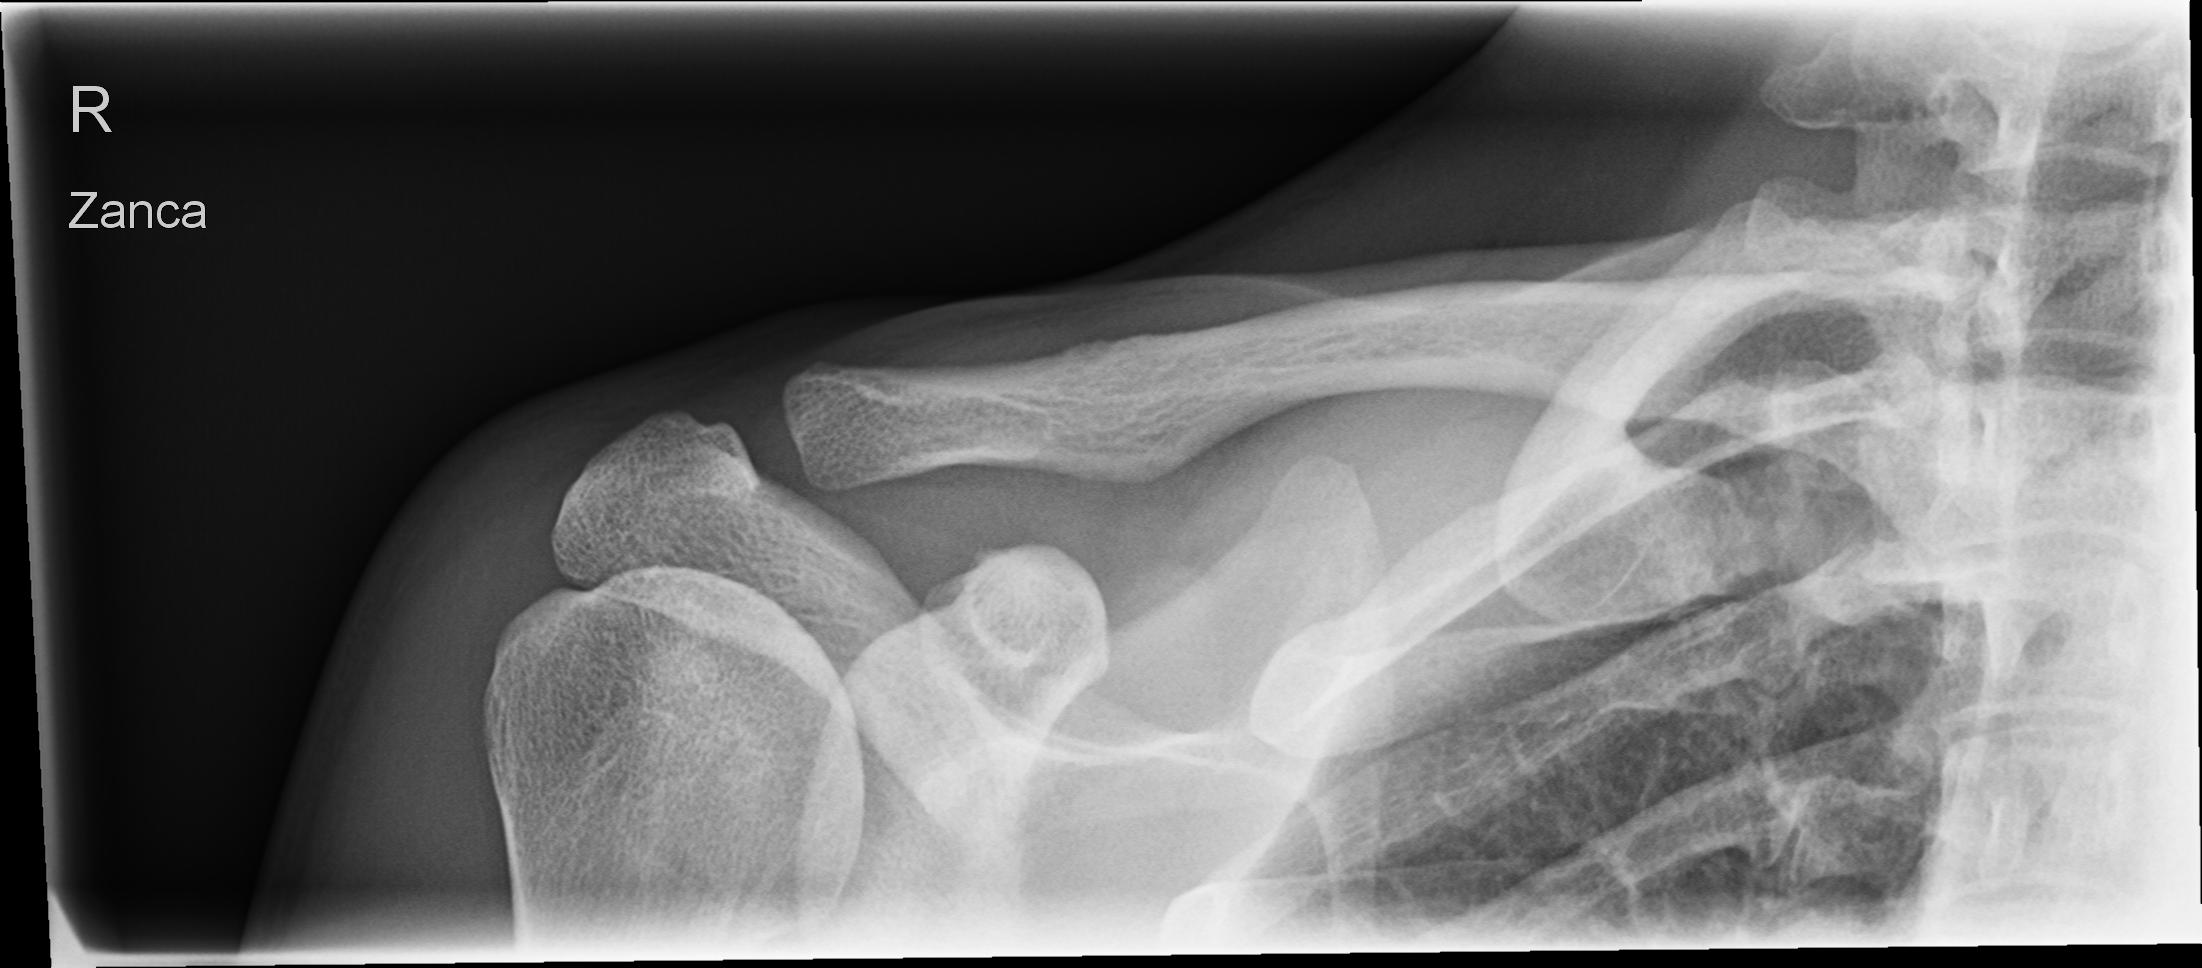

AC-Gelenk nach Zanca

Technik

• FDA: 1,15 m

• Ausgangsformat: 18/24 quer

• mit Raster

• Röhrenkippung: 30°- 45° caudo-cranial

Lagerung

Rückenlage am Stativ oder liegend auf dem Tisch

Kopf zur gesunden Seite drehen

Arme parallel am Körper

Zentralstrahl

30-45° caudo-cranial gekippt, auf Höhe des Acromioclaviculargelenk.

Bemerkung

Atemphase: Der Patient hält den Atem an.

Qualitätskriterien

Gut beurteilbare Darstellung des ganzen Schlüsselbeins und des Acromioclaviculargelenkes.